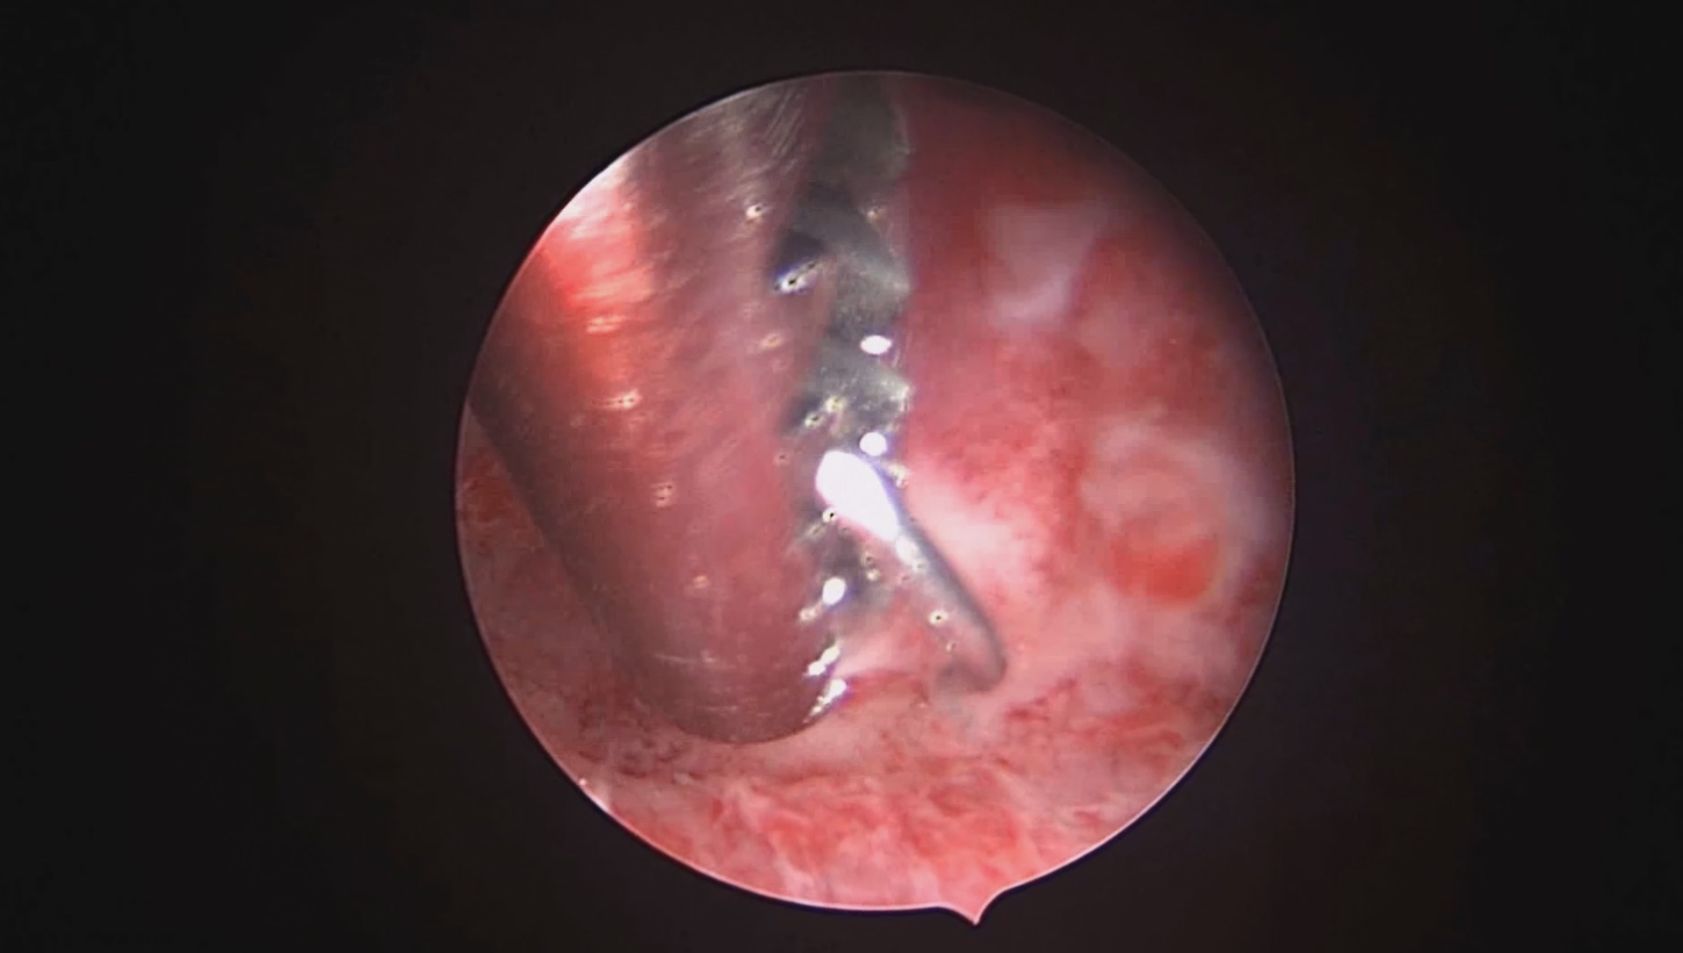

患者41岁,G4P2,顺产2次。因异常子宫出血于2023年12月在外院行宫腔镜检查,取内膜病检为增生晚期及分泌早期宫内膜组织,另见宫内膜息肉,术后药物治疗效果不佳,月经周期不规律。本次阴道不规则流血10+天,量多就诊。宫腔镜下尝试线结扣宫底锚定曼月乐,将结推人宫底肌层很困难,最后采用不锈钢挂钩固定。用曼月乐尾丝连接环与不锈钢挂钩,将挂钩插入宫底肌层,异物钳原位固定曼月乐,退出宫腔镜,结束手术。术后患者未回院复查节育环位置。